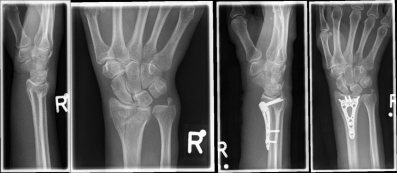

Pictures: A distal radius fracture with joint involvement (C-fracture) was treated with a plate osteosynthesis. After surgery, the plaster can be removed and physiotherapy exercises can be performed.